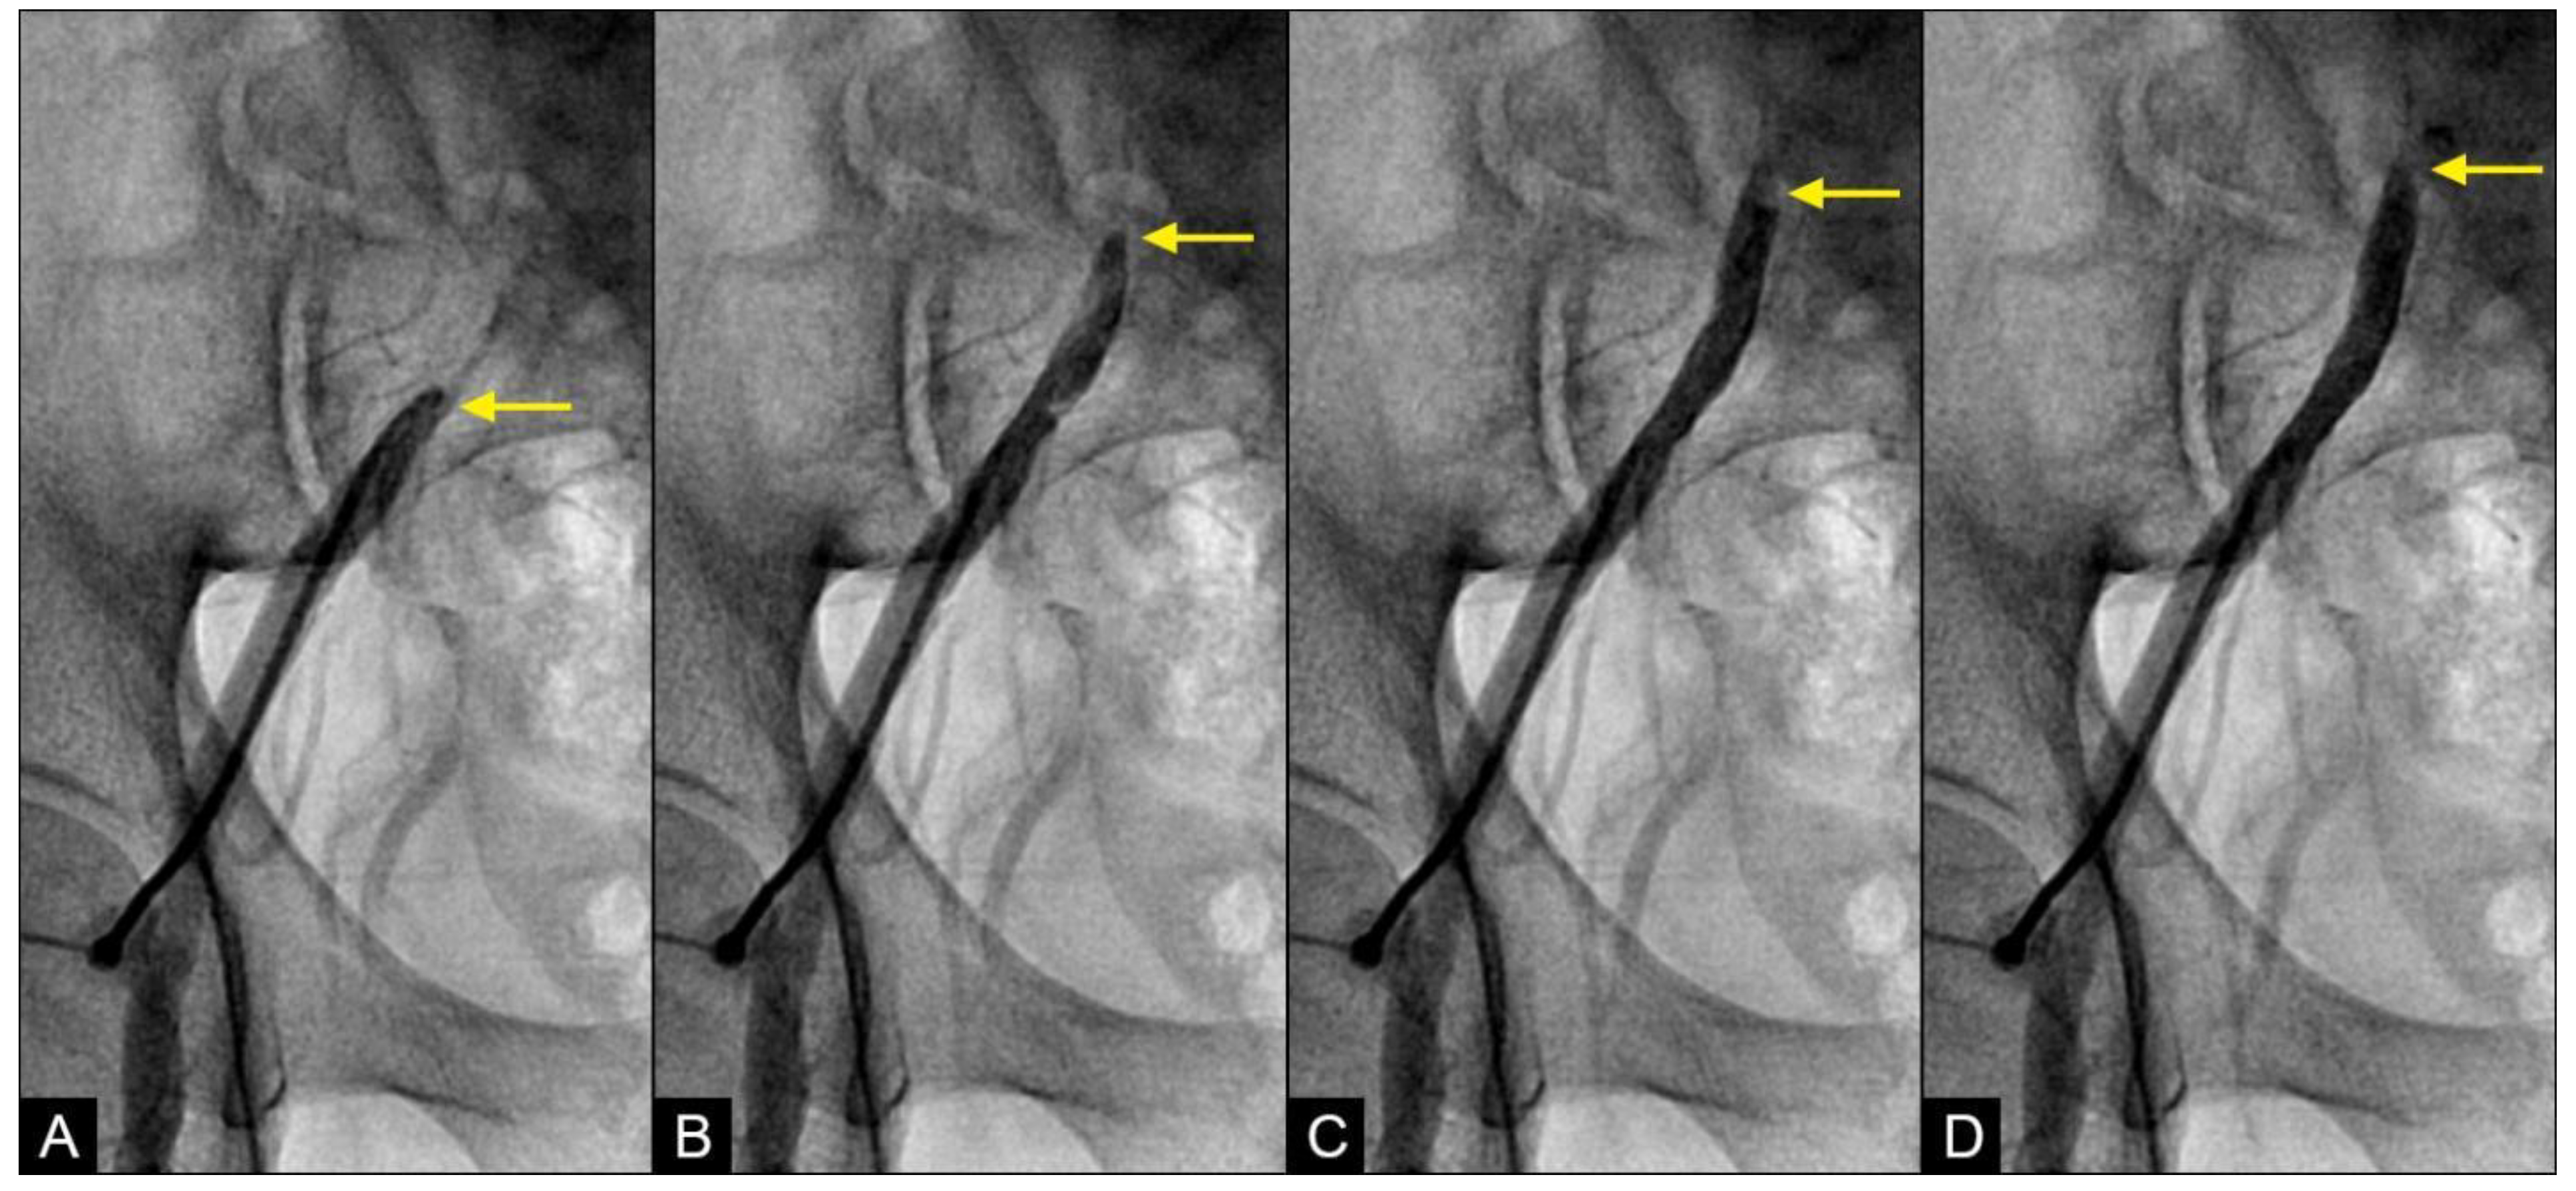

RETROGRADE contrast flow: In this iliac angiogram recorded by the novel dynamic angiographic technique, near the end of systole and in the first half of diastole, the retrograde flow is observed as a black contrast moving upwards from the iliac arteries towards the aortic bifurcation (Figure 6A–D). In contrast, for the right coronary artery (RCA), the retrograde flow happened mainly in the first half of systole. The retrograde flow in the coronary artery will be discussed in more detail in the next section.

Figure 6.

(A–D) Retrograde flow in the iliac artery. These are consecutive images separated from each other by 0.067 s. (A) Near the end of systole, the contrast (in black) could be seen moving upwards with a blunted, curved head (arrow). (B–D) In each image, separated by 0.67 s, the column of contrast was seen mixed with white-colored blood moving further up with a blunted, curved head (arrow).